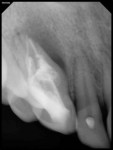

A 17-year-old healthy female was referred for the management of a persistent vestibular sinus tract in the periapical area labially in relation to the permanent maxillary right canine (tooth No. 6). The patient’s general dentist had started root-canal treatment of teeth Nos. 6 and 7 but did not complete the treatment. Tracer radiographic examination revealed the origin of the sinus tract to be in the apical end of an invagination with respect to tooth No. 6 (Figure 1 and Figure 2). This invagination extended into the root surface apically and was associated with large peri-invagination radiolucency.

The tooth was restored using light-cured composite resin (Z100™ Restorative, 3M ESPE, www.3MESPE.com). At the 12-month follow-up, the patient was asymptomatic with complete resolution of the sinus tract. A periapical radiograph revealed healing of periapical pathology (Figure 8).